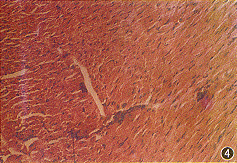

10~120天实验组和对照组昆明小鼠心肌均未见有病理改变;NIH小鼠除个别感染鼠心肌有变性外,未见有其它病理改变;Ba1b/c雄鼠和雌鼠在10~120天均发现有心肌变性、炎症、坏死、钙化和纤维化等病理改变。二者共同的特点为:10天和20天心肌病变以炎症和坏死为主(图1),钙化和纤维化较为少见;多数感染小鼠40天以后心肌病变以变性、钙化和纤维化为主(图2~4);心包炎和心包钙化在感染后各段时间均可见到。前20天心肌的病变雄性小鼠较雌性小鼠重。

图4 CVB3m感染Balb/c小鼠120天,心肌组织有钙化灶存在(HE染色 光镜 ×50)